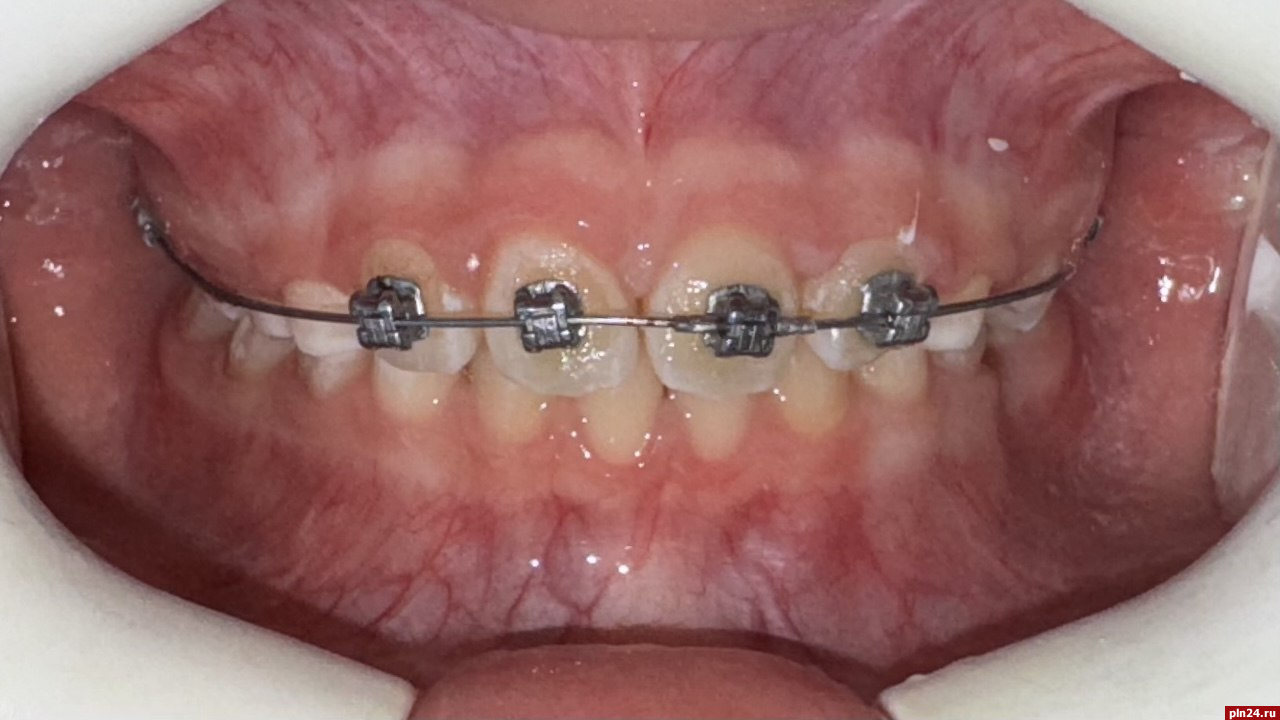

Частичная брекет-система – это вид несъемной ортодонтической аппаратуры, состоящей из отдельных замков (брекетов) и дуги, часто в пределах одной челюсти. Она устанавливается на постоянные зубы в сменном прикусе, когда часть из них остается молочными. Об этом рассказали специалисты Псковской стоматологической поликлиники на Октябрьском проспекте, 29.

В настоящее время чаще используются безлигатурные брекеты. За счет свободного расположения ортодонтической дуги, зубы, которые находятся в системе, испытывают меньшее напряжение при перемещении. Это позволяет уменьшить риски возможных осложнений. Такой вид фиксации позволяет сократить количество посещений к врачу-ортодонту без потери эффективности лечения.